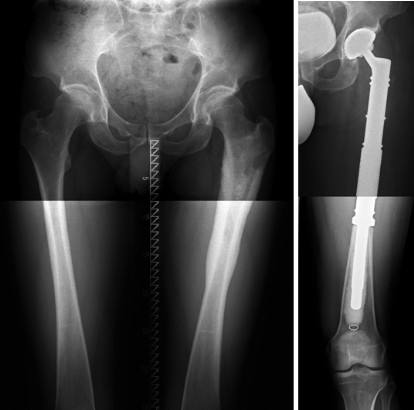

Ein Osteosarkom kann zwar prinzipiell an jedem Knochen auftreten, am häufigsten betroffen sind jedoch die gelenknahen Abschnitte der langen Röhrenknochen Zum Beispiel die OberschenkelKnochen oberhalb des Kniegelenks Etwas seltener entwickeln sich Osteosarkome im Bereich von Schienbein und OberarmKnochen. Informieren Sie sich über die Ursachen von Knieschmerzen, die von Bänderverletzungen bis zu Arthritis und Bursitis reichen, und erfahren Sie, wie Ärzte die Kniediagnostik behandeln. Das Osteoklastom ist ein halbbösartiger (semimaligner) Knochentumor Zwar zerstört er – wie bösartige Tumore – das umliegende Gewerbe, statt – wie gutartige Tumore – nur verdrängend zu wachsen Aber er bildet nur selten Metastasen ErwingSarkom Das ErwingSarkom ist die aggressivste Form des Knochenkrebses.

A leiomyoma, also known as fibroids, is a benign smooth muscle tumor that very rarely becomes cancer (01%) They can occur in any organ, but the most common forms occur in the uterus, small bowel, and the esophagus. Osteosarkom Der häufigste maligne Knochentumor betrifft meist die Altersgruppe zwischen 10 und 25 Jahren Er tritt in der Hälfte der Fälle knienah in Oberschenkelknochen oder im Schienbein auf Trotz frühzeitiger Streuung von Metastasen überleben mehr als 60 % der Betroffenen mindestens 5 Jahre. Im Jahr 1921 beschrieb James Ewing das Ewing Sarkom (ES) erstmals als "diffuses KnochenEndotheliom" (Ewing 1921).

Gutartige Knochentumoren unterscheiden sich in Ätiologie, Pathogenese und Pathophysiologie Angesichts der zeitlichen Assoziation zum physiologischen Knochenwachstum ist anzunehmen, dass ihr Wachstum durch die gleichen Prozesse mit beeinflusst wird Die meisten benignen Knochentumoren treten sporadisch auf, einige wenige auf dem Boden genetisch bedingter Prädispositionen (z B hereditäre. Ein Knochentumor ist eine Gewebemasse, die sich formt, wenn sich die knochenbildenden Zellen unkontrolliert teilen Eine wachsende Masse kann das gesunde Gewebe durch ein abnormes schwächeres Gewebe ersetzen Der Knochentumor kann verursachen einen Bruch der Knochenbälkchen (Trabekel), aus denen das Knocheninnere besteht, eine Fraktur. Endgültig zeigt ein Röntgenbild die typischen Veränderungen durch einen Knochentumor Bestehen Zweifel, ob es sich um gut oder bösartige Tumoren handelt, sind zusätzliche Untersuchungen notwendig, zum Beispiel eine Computertomographie ( CT ) oder eine Magnetresonanztomographie ( MRT ).